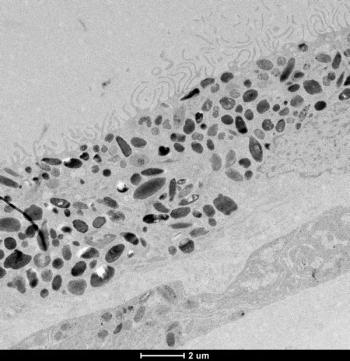

Tunde Peto, MD, PhD, discussed two of her presentations at EURETINA 2022: "UK Biobank retinal imaging grading: methodology, baseline characteristics and findings for common ocular diseases" and "Retinal phenotyping of different variants of Alzheimer’s disease using ultra-widefield imaging."